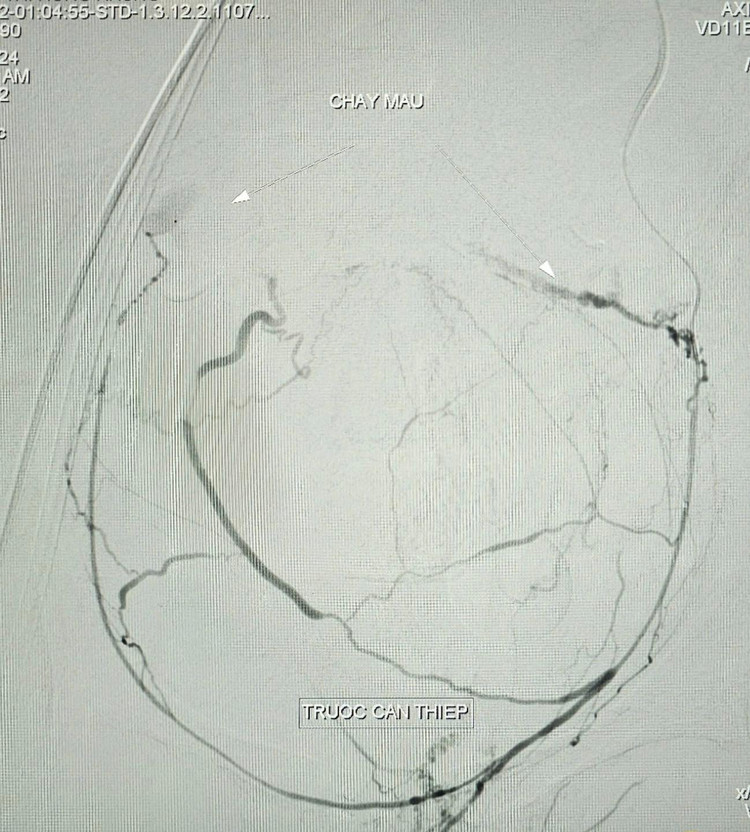

Kết quả chụp cắt lớp vi tính ổ bụng có cản quang ghi nhận hình ảnh ổ thoát mạch.Bệnh nhân có chỉ định chụp và nút mạch điều trị cầm máu các tạng số hóa xóa nền cấp cứu (DSA).

BS.CKII. Trần Công Khánh, Phó khoa Chẩn đoán hình ảnh và ê-kíp thực hiện, kết quả ghi nhận tăng sinh nhiều nhánh động mạch chậu trong hai bên, tổn thương co thắt mạch kèm ổ thoát thuốc vùng tiểu khung được cấp máu từ nhánh chậu trong trái, xác định vị trí và tiến hành bơm tắc bằng hỗn hợp keo, chụp kiểm tra ghi nhận không còn ổ thoát mạch, sinh hiệu bệnh nhân ổn định được chuyển khoa Hồi sức tích cực – Chống độc tiếp tục theo dõi.

Trưa ngày 02/10/2024, bệnh nhân có dấu hiệu xuất huyết nội tái phát và được chỉ định chụp cắt lớp vi tính bụng có cản quang kiểm tra phát hiện ổ thoát mạch, các bác sĩ tiến hành chụp và nút mạch điều trị cầm máu các tạng số hóa xóa nền (DSA) lần thứ hai. Kết quả ghi nhận hình ảnh thoát mạch được cấp máu từ nhánh động mạch mạc treo tràng trên, xác định vị trí tiến hành bơm tắc bằng hỗn hợp keo, thủ thuật tiến hành 40 phút, bệnh nhân ổn định tiếp tục hồi sức tích cực.

| Hình ảnh chảy máu trên phim chụp trước và sau can thiệp - Ảnh BVCC |